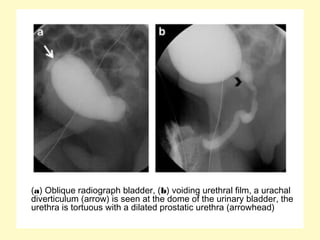

(a) Oblique radiograph bladder, (b) voiding urethral film, a urachal

diverticulum (arrow) is seen at the dome of the urinary bladder, the

urethra is tortuous with a dilated prostatic urethra (arrowhead)